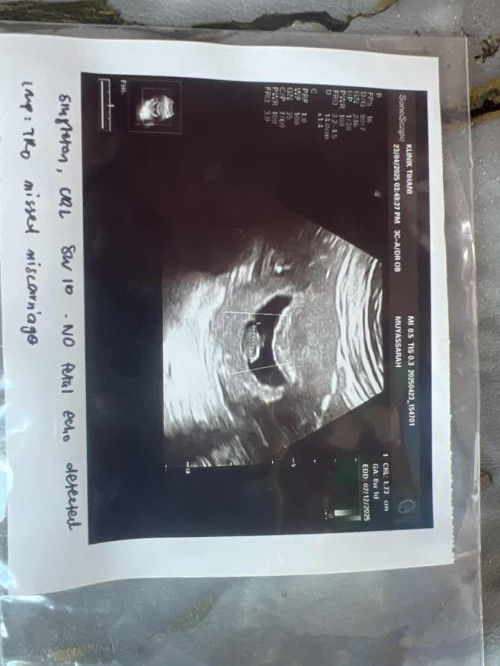

Salam semua mommies, sy nak tanya haritu masa 6 weeks saya dah pergi scan. Baby okay ada heartbeat dah time tu. Harini saya pergi scan 8 weeks baby ada. Size baby pun sama dengan tarikh. Tapi heartbeat takda. Sy takda bleading apa apa. Doc risau jika saya missed miscarriage. Tapi suruh repeat scan lagi 2 minggu. Tolong la bagi support. Sy sedih ni 🥲

Nanti sy repeat scan dekat klinik lain